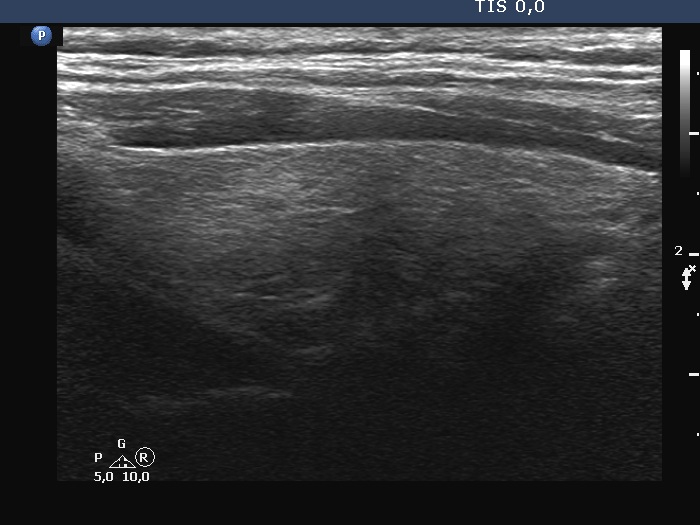

Examination 7 months later (second row of images):

Clinical presentation: The patient became asymptomatic within 12 hours after the first dose of methyl-prednisone and remained so.

Palpation: no abnormality.

Laboratory tests: TSH 1.03 mIU/L, FT4 14.2 pM/L, CRP 0.7 mg/L.

Ultrasonography: Both the size of the nodule and the extent of hypoechoic areas have decreased. An isoechoic nodule has appeared which was obscured by hypoechogenicity in the previous study. The vascularity was still very scanty.

Suggestion. Follow-up in 2 years.